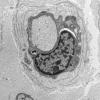

PERIPHERAL NEUROPATHY

18 HEREDITARY DISORDERS

Charcot-Marie-Tooth 3 (CMT-3) (2)